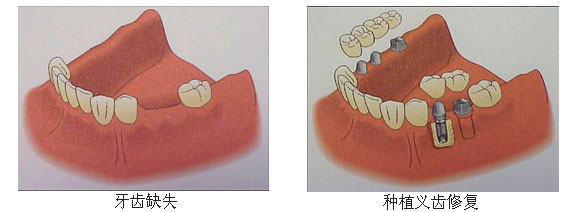

如果牙齿缺损伤及牙根,无保留可能——可选微创即刻种植牙

康贝佳微创即刻种植牙采用先进口腔CT全景诊疗及3D导板,结合微创技术精准植入种植体,实现即拔即种、术后即可简单饮食的种植效果。